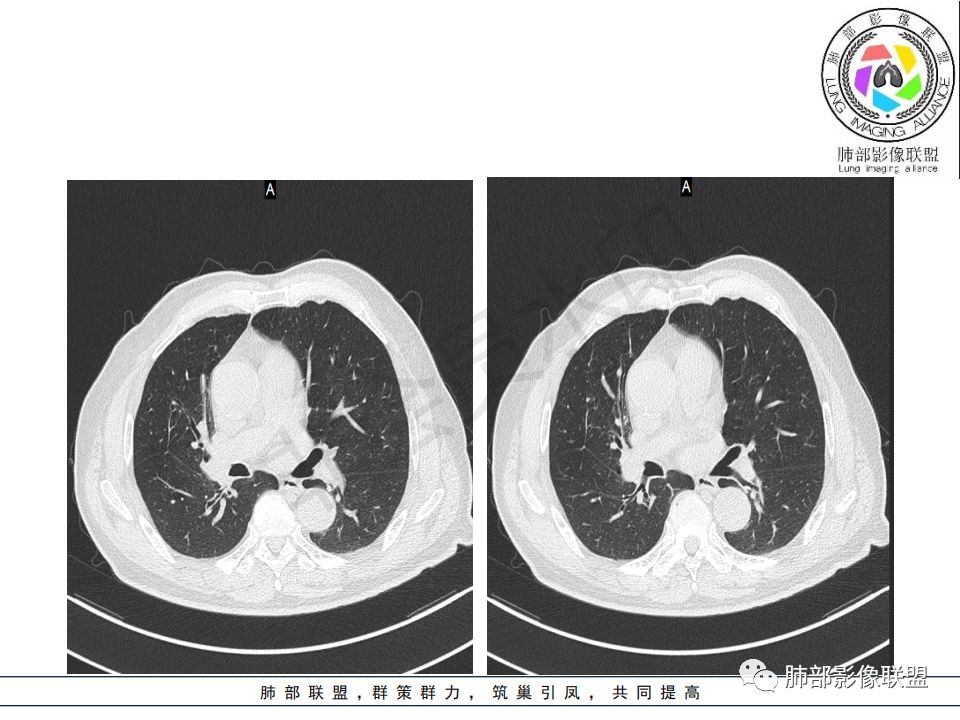

右肺主支气管内外软组织影,支气管变窄截断,右肺上叶成软组织密度,其内见细沙样钙化,周围看见小结节,右肺门看见一淋巴结稍大,增强不均匀强化,胃癌病史,考虑:转移,或原发肺恶性鳞癌。

又是一个支气管腔内占位,按常规,右肺上叶支气管占位,突入腔内,上叶不张,恶性没问题,鳞癌可能,但这么大,坏死少,是个疑点

如果鳞癌这么大,破坏力应该很大吧,肋骨会不会受累?当然这例气管壁受累,截断,远端阻塞性肺不张,还是符合中央型肺癌,特别是鳞癌的

晨读病例:老年男性,症状轻,右侧胸廓略塌陷,右肺主支气管内外软组织影,支气管变窄截断,右肺上叶不张,其内见细砂样钙化,周围看见小结节,右肺门看见一淋巴结稍大,增强不均匀强化,胃癌病史,常规考虑:转移,或原发肺恶性鳞癌。鉴别支气管TB?